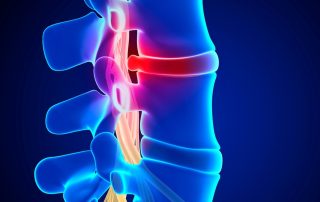

Omurgada Sinir Sıkışması Nasıl Anlaşılır?

Sinir sıkışmasının belirtileri ve tanı yöntemleri. Uyuşma, karıncalanma, güç kaybı ve yayılan ağrı sinir sıkışmasının tipik belirtileridir. Uyuşma, karıncalanma, güç kaybı ve ağrı sinir sıkışmasının tipik belirtileridir. Omurgada sinir sıkışması, çoğu zaman “belim ağrıyor” gibi genel bir şikâyetten çok daha spesifik işaretler verir. Çünkü problem kas veya eklem kaynaklı lokal ağrı değil; omurgadan çıkan sinirin baskı altında kalmasıdır. Bu durumda vücudun verdiği sinyaller daha “sinir hattı boyunca” ilerler: uyuşma, karıncalanma, yayılan ağrı ve bazen güç kaybı. Sinir sıkışmasının tipik belirtileri nelerdir? Sinir sıkışmasında en sık görülen belirtiler şunlardır: 1) Uyuşma ve karıncalanma Parmaklara, ayağa, bacağa veya kola yayılan uyuşma-karıncalanma sinir [...]